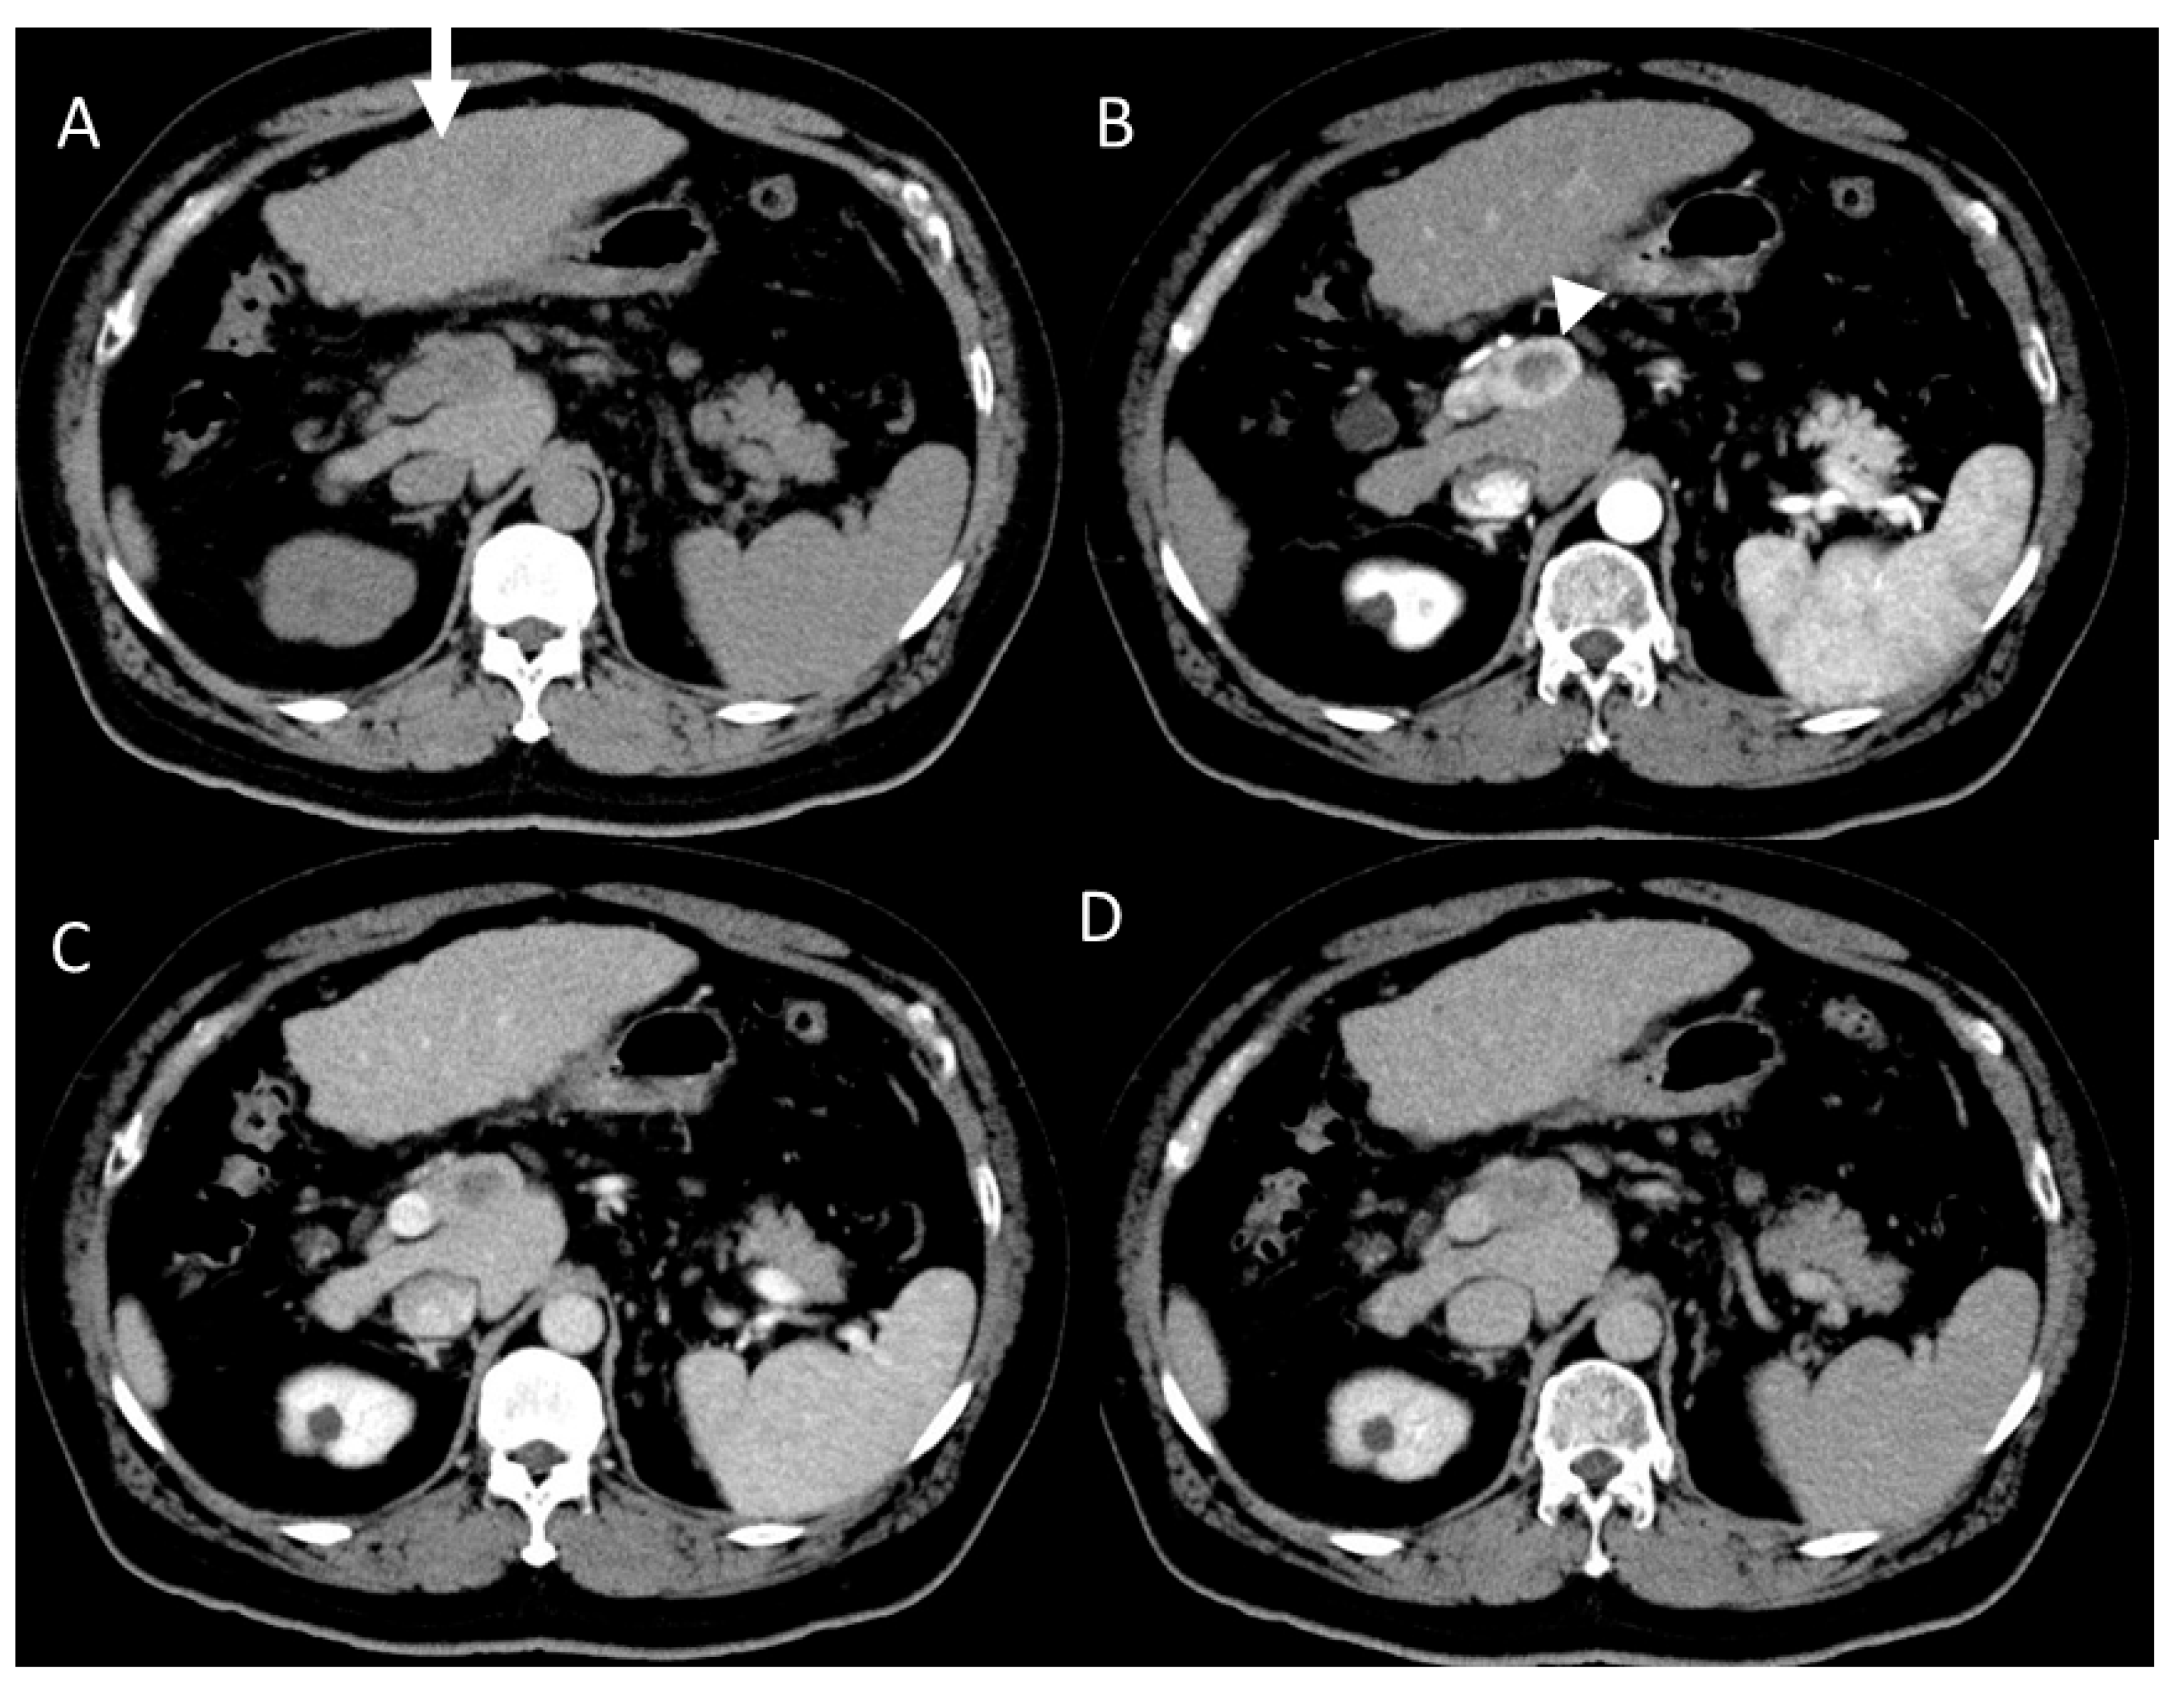

4.7. Combined Hepatocellular and Cholangiocarcinoma (cHCC-CCA)

4.8. Steatohepatitic HCC (SH-HCC)